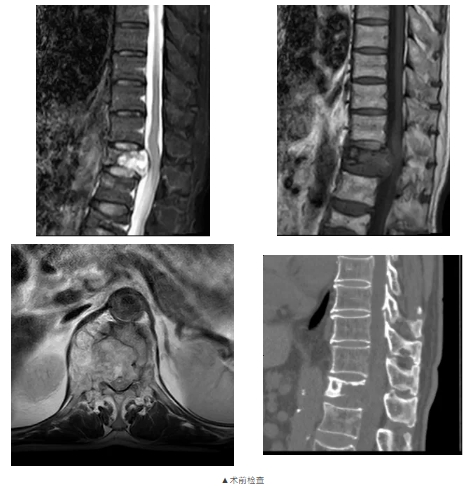

原来在一年前,黄老因罹患肾脏肿瘤行左肾切除术,但术后病理不详。脊柱外科(骨四科)主任姜树东在得知这一情况后,立即为患者完善胸腰椎核磁共振检查。结果提示T12椎体骨质破坏,结构不完整,向后压迫硬膜囊,椎管狭窄,脊髓受压;周围软组织肿胀;考虑病理性骨折(T12),脊柱转移瘤可能性大。随后,再行T12椎体穿刺活检术。同时患者家属提供了患者的既往病历:左肾肿瘤符合透明细胞癌。

椎骨活检病理结果显示:(T12椎体内组织)送检少许破碎骨组织、多量纤维结缔组织及纤维素渗出坏死组织。纤维结缔组织部分间质疏松水肿,部分区域细胞密集,局灶可见透明细胞浸润。结合病史及免疫组化结果,符合肾透明细胞癌转移。

综合患者各项检查结果,姜树东带领脊柱外科(骨四科)医疗团队开展病情讨论。患者高龄,合并脊柱转移癌,病理性骨折,椎管狭窄,左肾切除术后,肾恶性肿瘤病史诊断明确。为缓解患者症状,提高生活质量,经与患者及家属充分沟通,考虑行脊柱手术治疗。